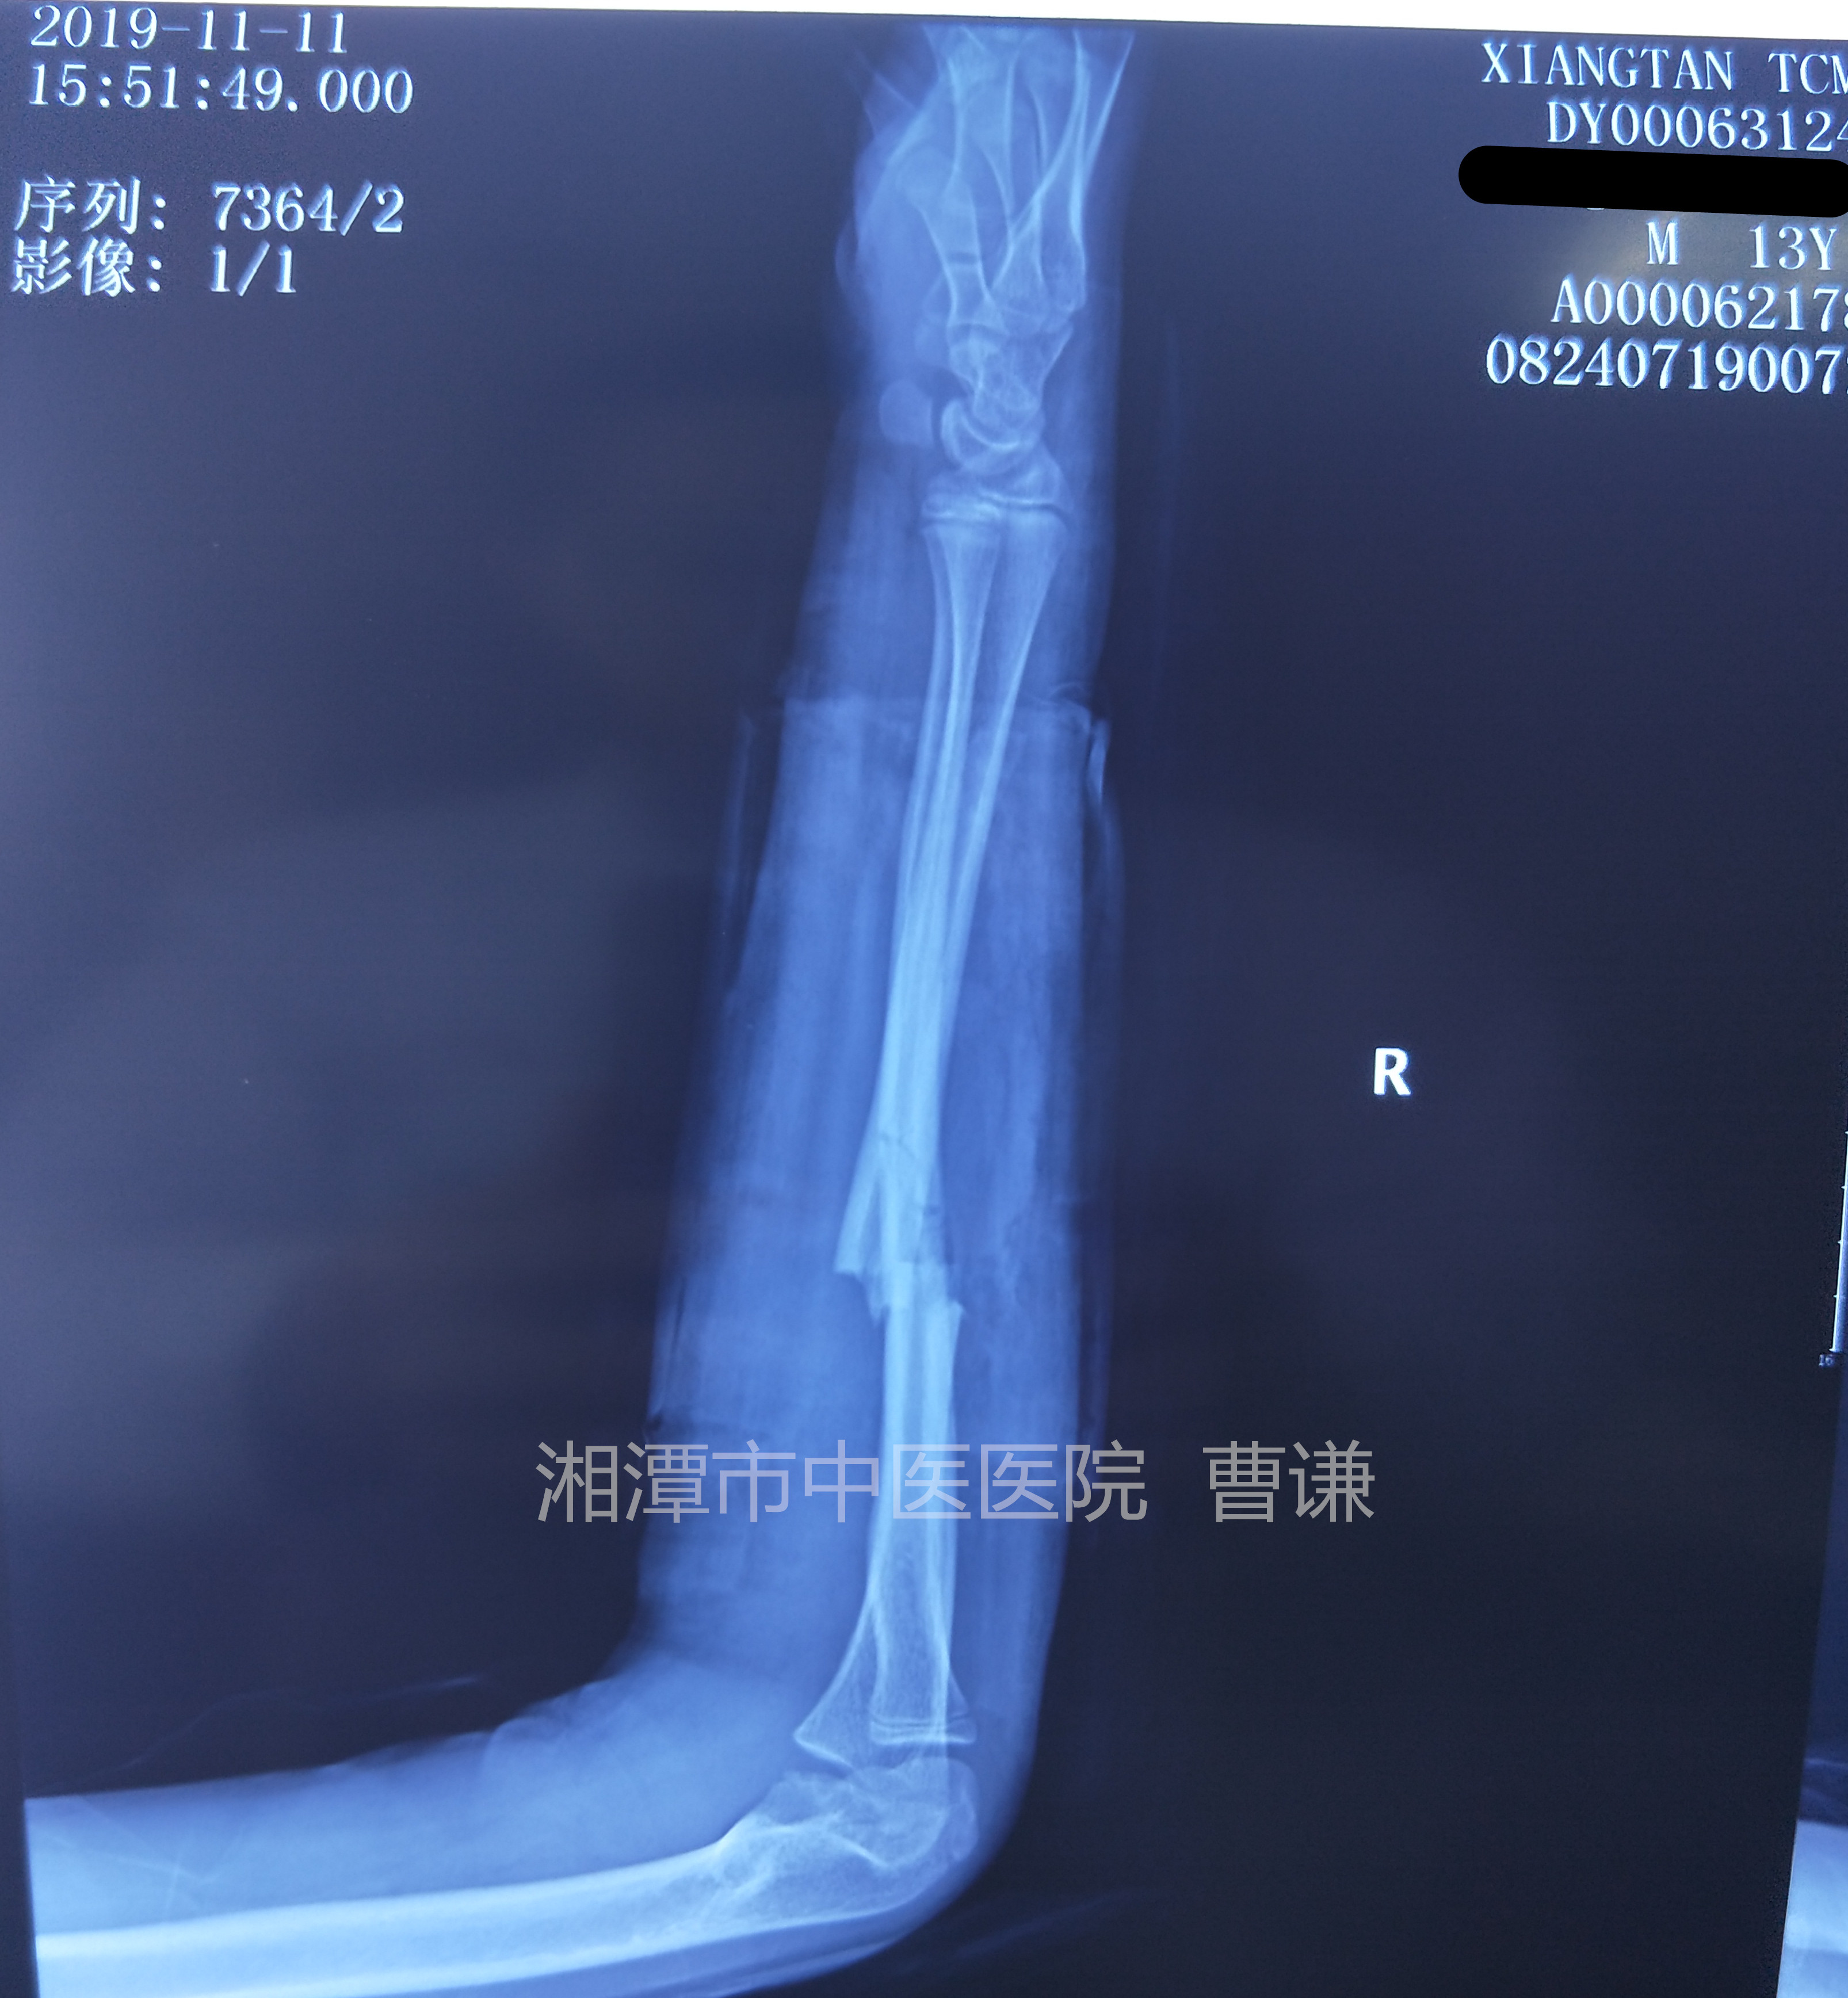

固定后拍片复查,是不是觉得比之前的片子对位对线情况更差了?有问题吗?没有问题,可以继续保守治疗!